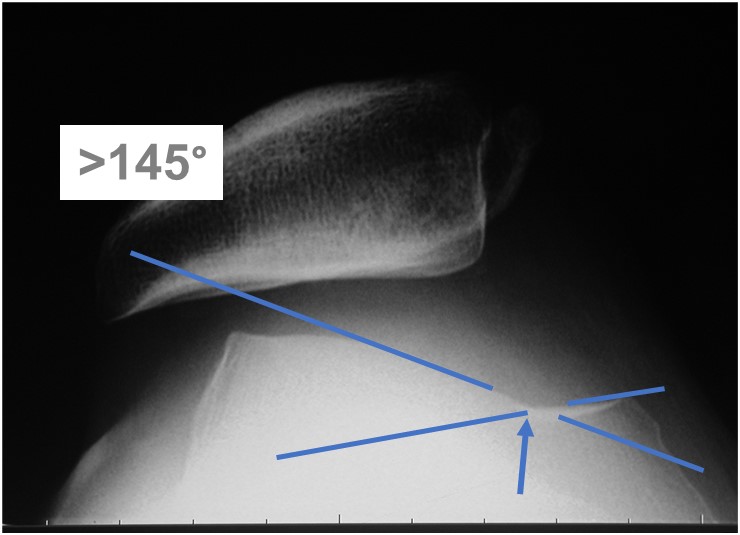

股骨滑车即图中所示股骨内外髁之间的向内凹陷的沟,正常屈膝过程中髌骨在此沟内滑动,在Menchant 位(屈膝45°的髌骨轴位片)上看滑车沟内外侧关节面的切线成角,即滑车沟角一般都<145°;而髌骨脱位患者股骨滑车沟往往发育的浅平,滑车沟角>145°,导致髌骨容易脱位。

图4. 髌骨脱位患者的Merchant位髌骨轴位片显示股骨滑车沟角>145°